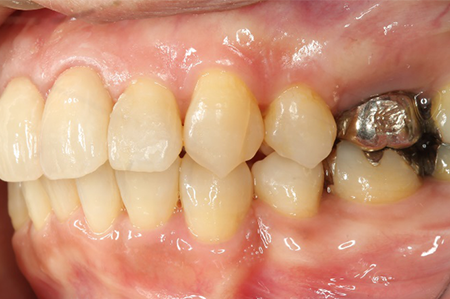

この患者様は長い事歯科医院には通っておらず、下の歯は前歯以外は全て崩壊していることが分かります。

前から見ても歯が欠けてしまい、歯茎も赤く腫れてしまっているのが分かります。

一般的には入れ歯が妥当かと思われますが、患者様は33歳、まだまだ人生は長いです。

奥歯がないと前歯でしか噛めなくなってしまい、残っている前歯もいずれダメになってしまいます。

また、奥歯がなくなってからの期間が長かったため、入れ歯が入るスペースが奥にないのが分かります。

様々なことを鑑み、患者様とも何度も話し合いを行い、下の奥歯には必要最低限のインプラントを、他の歯も外科処置を施しなるべく歯を抜かない方法を取りました。

最終的に抜歯した本数は下の歯5本。上の歯に関しては全て残すことが出来ました。

奥歯があることで前歯の負担を減らし、前歯を失うリスクを下げることが出来ます。